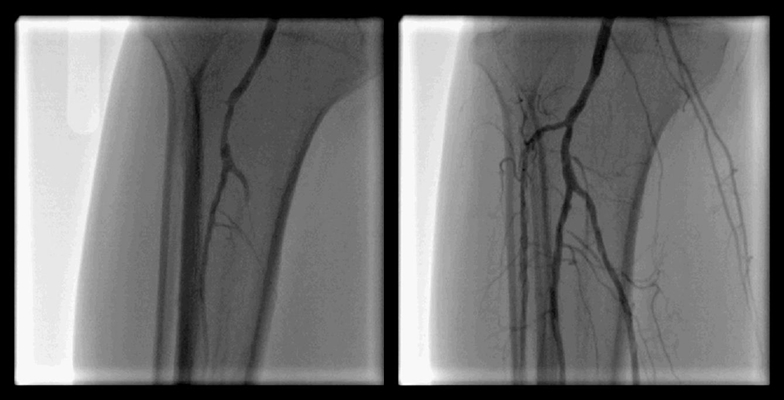

- 大動脈狭窄 【写真】

- 高位大動脈閉塞(Leriche synd) 【写真】

- 腸骨動脈完全閉塞(右) 【写真】

- 腸骨動脈狭窄 【写真】

- 浅大腿動脈狭窄 【写真】

- 浅大腿動脈閉塞 【写真】

- 3枝閉塞 【写真】

- 脛骨腓骨動脈幹(peroneal trunk) 【写真】

- 後脛骨動脈(posterior tibial artery) 【写真】

- 腎動脈 【写真】

- 鎖骨下動脈 【写真】